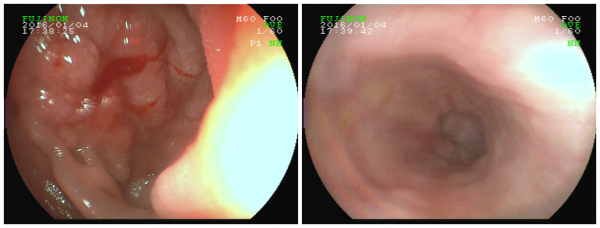

• 小小牙签竟酿大祸瑞康无痛胃镜异物取出术为男子解忧

小小牙签竟酿大祸瑞康无痛胃镜异物取出术为男子解忧

要不是在瑞康医院做了胃镜下异物取出术,林先生还不知道导致自己腹痛一个多星期的罪魁祸首竟然是藏在十二指肠球降交界处约6.5cm长的牙签! ...